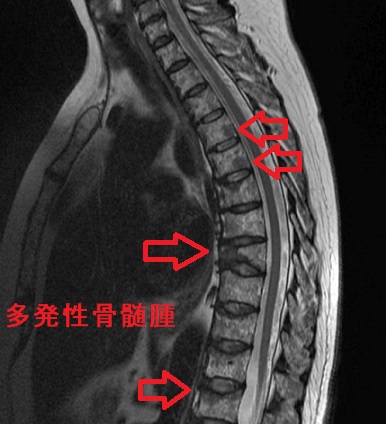

多発性骨髄腫では、骨中の骨髄(赤血球、白血球、血小板を作る場所)にて、がん化した形質細胞(Bリンパ球が分化した細胞)[腫瘍性形質細胞]が周囲の骨を破壊しながら増殖します。

- 骨髄腫細胞で産生されるIL-6 [インターロイキン6(Interleukin-6)]が、破骨細胞を活性化させて骨破壊が生じます。腰背・肋骨などの骨痛は安静時に軽く、体動時は強く、場所も移動します。NSAID 無効の腰痛にて、体動と自力歩行が困難になるケースも(オピオイド投与)。痛み無く、骨折で発見される事もあります。(甲状腺機能亢進症/バセドウ病の骨融解による骨痛、甲状腺癌の骨転移痛、原発性副甲状腺機能亢進症の線維性骨炎と鑑別。)

- 骨が溶け出し、血液中のカルシウム濃度が上昇(高カルシウム血症)→意識障害・腎障害に至ります(大量生理食塩水輸液+ビスホスホネート製剤投与)[局所性骨溶解性高カルシウム(Ca)血症(local osteolytic hypercalcemia: LOH)]。